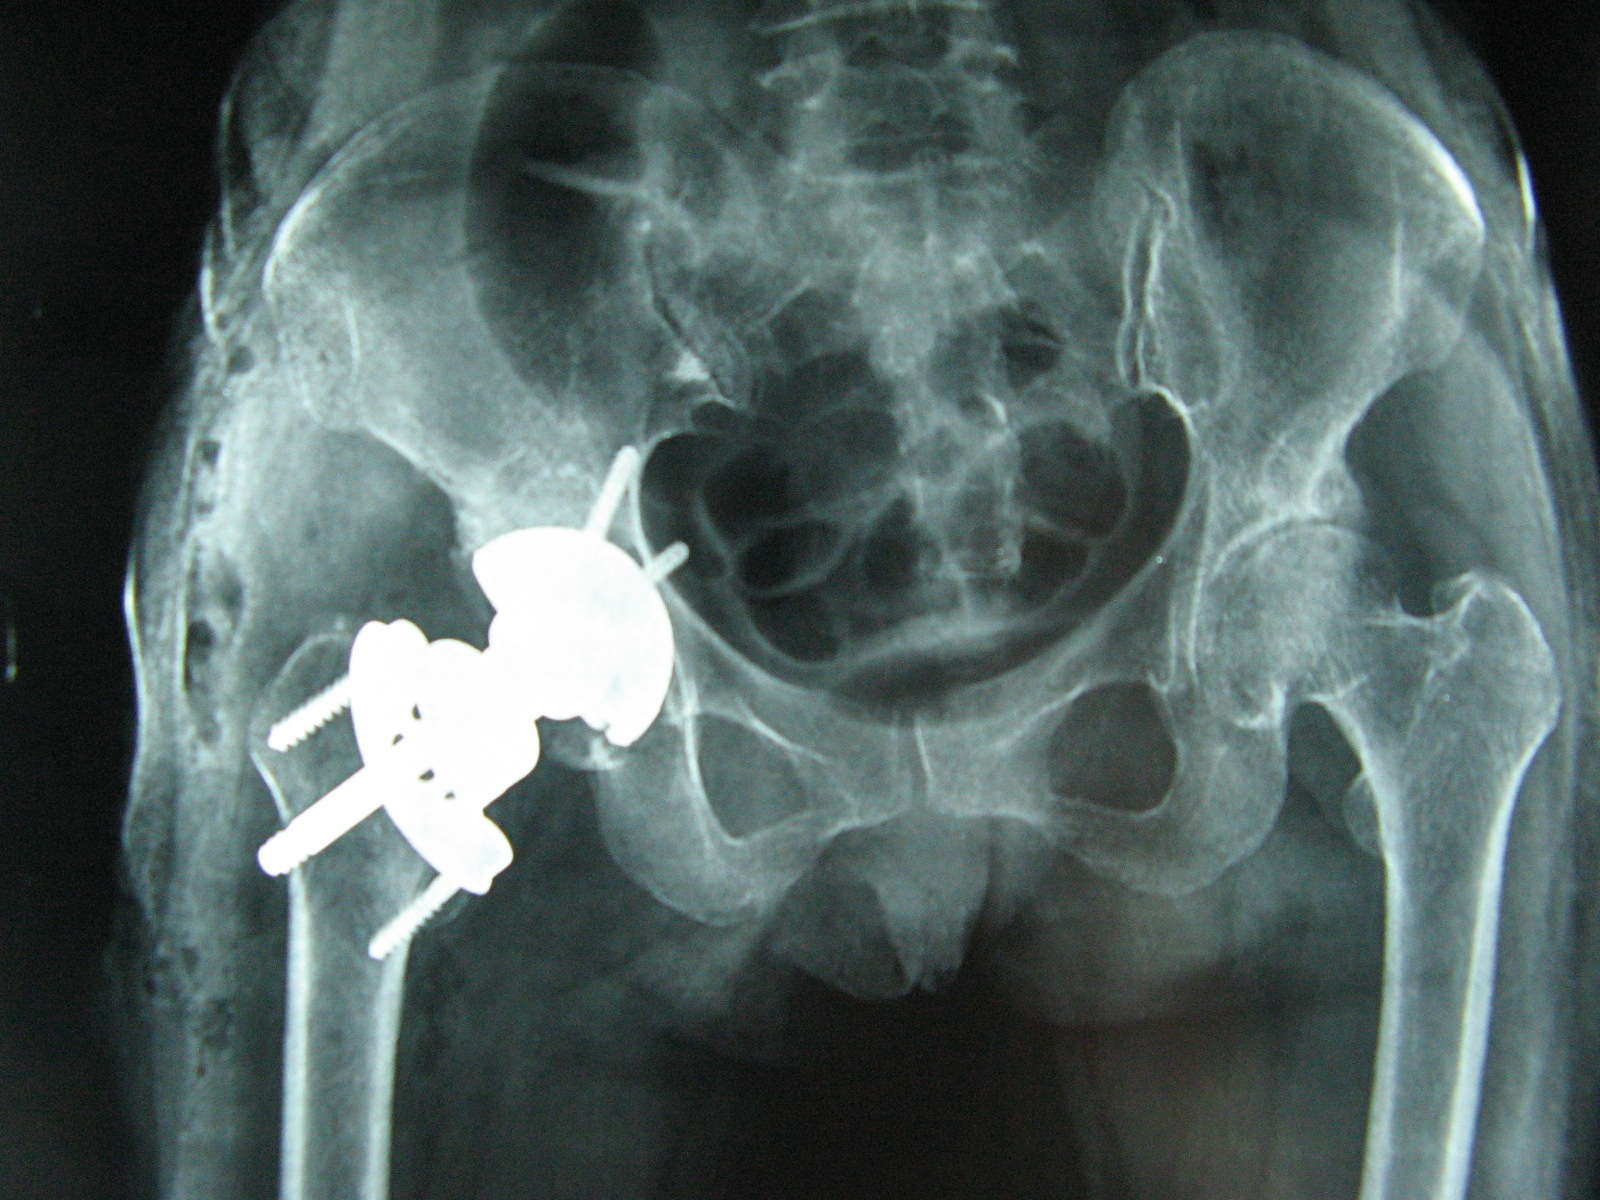

自己做的第一例全髋,请大家指点 [病例帖]

图片尺寸888x666